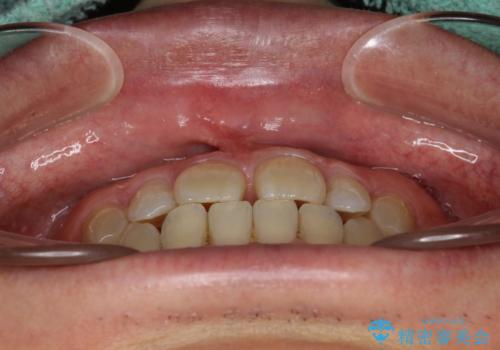

前歯の真ん中の隙間を閉じたい インビザラインによる目立たない矯正

- 上顎の正中の隙間が気になるとのことで来院されました。

下の歯と歯の間をわずかに削り、スペースを作り、正中の隙間を閉じる計画としました。

装置はインビザラインにて行いました。

インビザラインで目立たずに矯正治療を行うことができました。

使用時間を守っていただけたので、比較的スムーズに矯正を終了することができました。